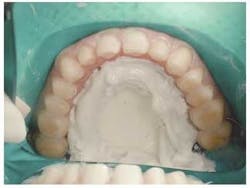

Using a matrix made by the laboratory from an ideal wax-up, the patient's teeth were temporized with Luxatemp. This allowed us to verify the proposed case in many ways. Size and shape of teeth, incisal edge position, approximate color, and others are all benefits of custom temporaries.

When the case arrives back from the lab, I always evaluate it on the models checking on fit, shape, and color. Now, it is time to place the new sculptures on the teeth.